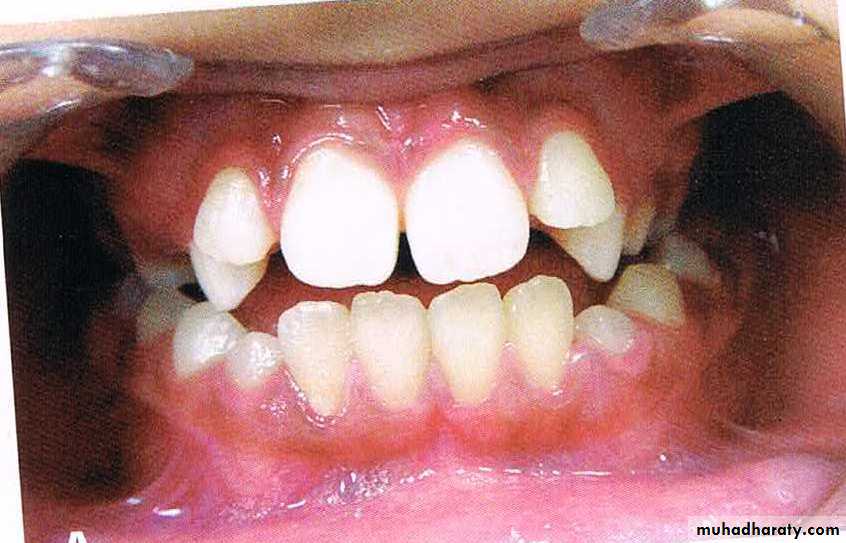

Angle’s class I malocclusion is characterized by the presence of a normal inter-arch molar relationship. The mesio-buccal cusp of the maxillary first permanent molar occludes in the anterior-buccal groove of mandibular first permanent molar.

The patient may exhibit dental irregularities such as crowding,spacing,rotations,missing tooth,etc.

Class I malocclusion

Approximately 60%-70% of all cases of malocclusion fall into this class.

Class I malocclusion (continued…)FEATURES OF CLASS I MALOCCLUSION

1. Class I molar canine incisor relationship